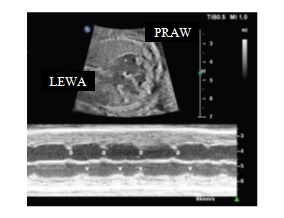

Ciężarna w 31 tygodniu ciąży została skierowana na badanie echokardiograficzne płodu z powodu nieregularnej czynności serca płodu widocznej w badaniu ultrasonograficznym. Na podstawie badania M-mode tego płodu rozpoznać należy:

Ciężarna 30-letnia, wywiad rodzinny nieobciążony, została skierowana na badanie echokardiograficzne w 24 tygodniu ciąży z powodu bradykardii 70 ud/min. Obraz M-mode oraz przepływ w tętnicy środkowej mózgu u tego płodu przedstawiono poniżej. Wskaż stwierdzenie prawdziwe dotyczące opisanego przypadku: